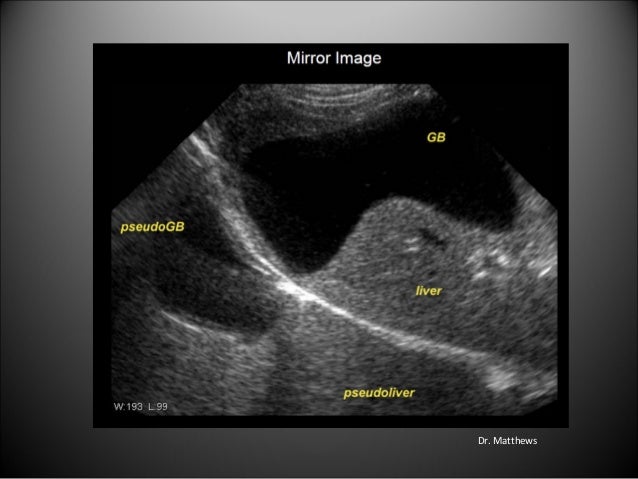

40+ Mirror Image Artifact Ultrasound Bladder Images. Emergency physicians performing these studies need to be cognizant of artifacts produced by ultrasound technology, as they can lead to misdiagnosis. Mirror image artifact in sonography is seen when there is a highly reflective surface (e.g.

Mirror image artifact in sonography is seen when there is a highly reflective surface (e.g.